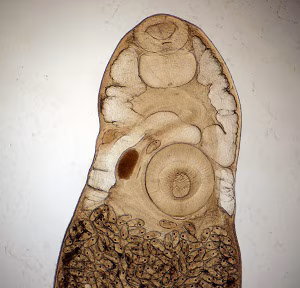

Philophthalmiasis image

Figure A: Carmine-stained adult specimen of P. gralli. Features noted here include the oral sucker (OS), pharynx (PH), cirrus pouch (CP), ventral sucker/acetabulum (VS), uteri containing eggs (UT), ovary (OV), and testes (TE).